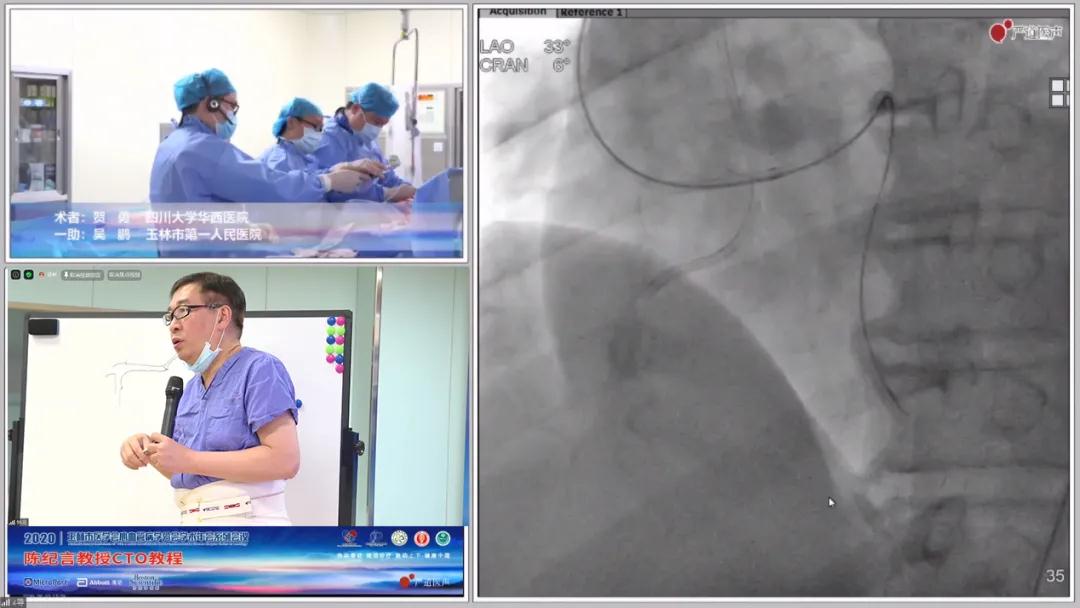

手术演示精彩转播

IVUS辅助下的reverse CART

送入ASAHI SION blue冠脉内钢丝至圆锥支,沿钢丝送入IVUS到圆锥支,证实到位后进行血管内超声检查找到可疑右冠脉闭塞处,送入KANEKA双腔微导管,沿微导管送入conquest pro冠脉内钢丝,cp反复尝试突破闭塞段开口,更换fighter导丝采用knuckle技术内膜下行走到闭塞段远段。

IVUS指导下的reverse CART

病例复盘:

贺勇教授在术后总结中谈到,此次病例的困难之处在于一直没有找到入口,最后使用了IVUS才明确入口位置在残端偏上,经过尝试后果断选择reverse CART策略。

做reverse CART时一定要明确导丝的机制,最好是有IVUS引导,如果没有IVUS辅助,要大致判断导丝位置。正向导丝通过Knuckle技术在内膜下,逆向导丝此时位置较高,判断在斑块内。这个时候选择reverse CART器械十分重要,需要逆向导丝足够锋利,因为正向在内膜下,逆向在斑块内,换了CP导丝在球囊辅助下一针成功。